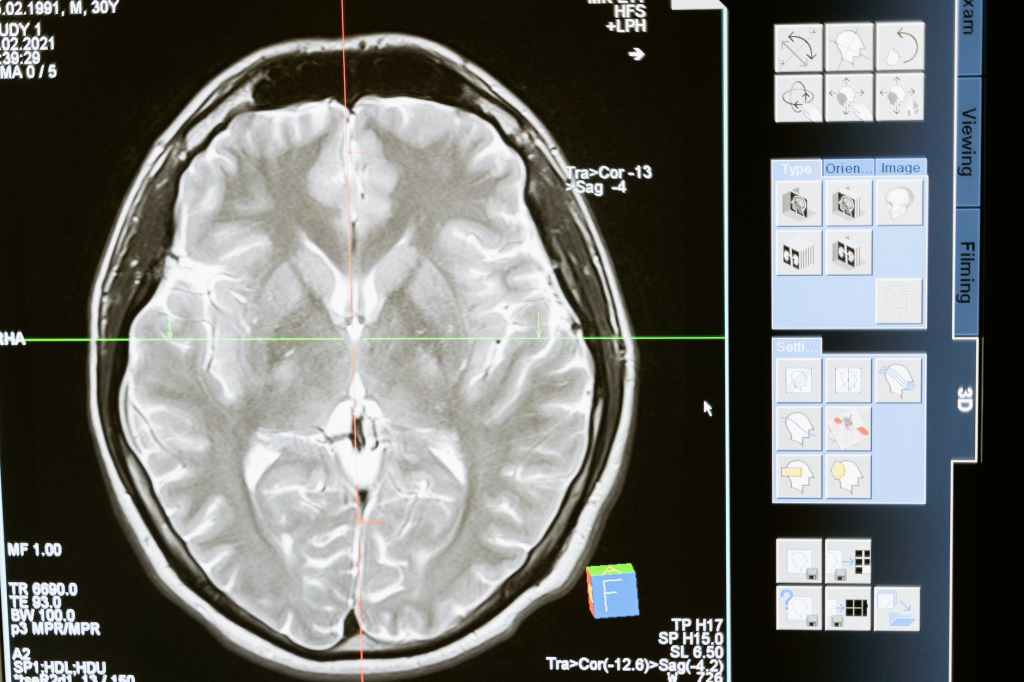

Scientists have found that feelings of exhaustion and stress tend to result in experiences of déjà vu, but questions remain as to why our brains respond to those areas of fatigue with feelings of déjà vu. While there are multiple theories explaining déjà vu, they all share a common theme: the temporal lobe. The temporal lobe is the section of the brain that controls memory, and when your body is under immense amounts of stress, the temporal lobe cannot function properly. As a result, the hindrance of the temporal lobe can cause these episodes or feelings of déjà vu to occur.

While connecting déjà vu to memory retention still needs further research, scientists developed this shared understanding from people who suffer from temporal lobe epilepsy. Temporal lobe epilepsy is a condition where nerve cell activity in the brain is disturbed. Results from these studies suggest that déjà vu events may be caused by an electrical malfunction in the brain. For those with temporal lobe epilepsy, clinical reports show that some of these patients experience déjà vu before an epileptic seizure event (Neuroscience News, 2016).

It is found that seizure discharges from the temporal cortex simultaneously activate two circuits in the hippocampus. One of these circuits represents our ongoing experience of the present world while the other retrieves memories (Chauvel, 2017). By activating both these circuits at the same time, it is possible that these two brain functions colliding cause us to remember the present situation, or, in other words, experience déjà vu.